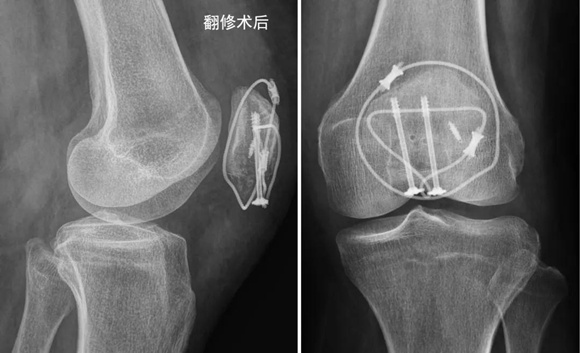

张志山医生决定选择新设计的φ3.0mm垫片空心钉组成的新型张力带系统来做翻修手术。术中见钢丝和克氏针已经松脱,部分髌腱撕脱,下极骨折块粉碎。小心复位骨折,拧入带异形垫片的φ3.0mm空心钉(如图)。

异形垫片的小孔穿入钛缆,钛缆穿过髌骨近端的骨洞,在髌前呈8字拧紧,钛缆、异形垫片和空心钉形成一体化的牢固张力带。锚钉修复撕裂的髌腱,钛缆环扎髌骨一圈(如图)。

固定完成后,术中屈伸膝关节,见内固定物很牢固。

洪女士术后恢复顺利,经过艰苦的功能练习,膝关节活动良好,术后2个月骨折愈合,洪女士恢复了正常生活。